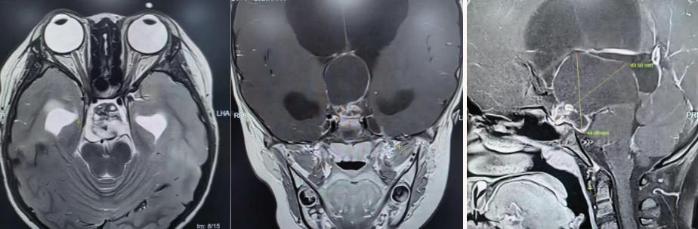

术前核磁共振检查。

为精准掌握肿瘤情况,团队为欢欢完善了垂体MRI平扫+增强检查及相关激素水平检测。结果显示:肿瘤体积超过4厘米,形如鸡蛋,已严重压迫视神经与垂体,突入第三脑室,并与周围重要神经血管结构紧密粘连。